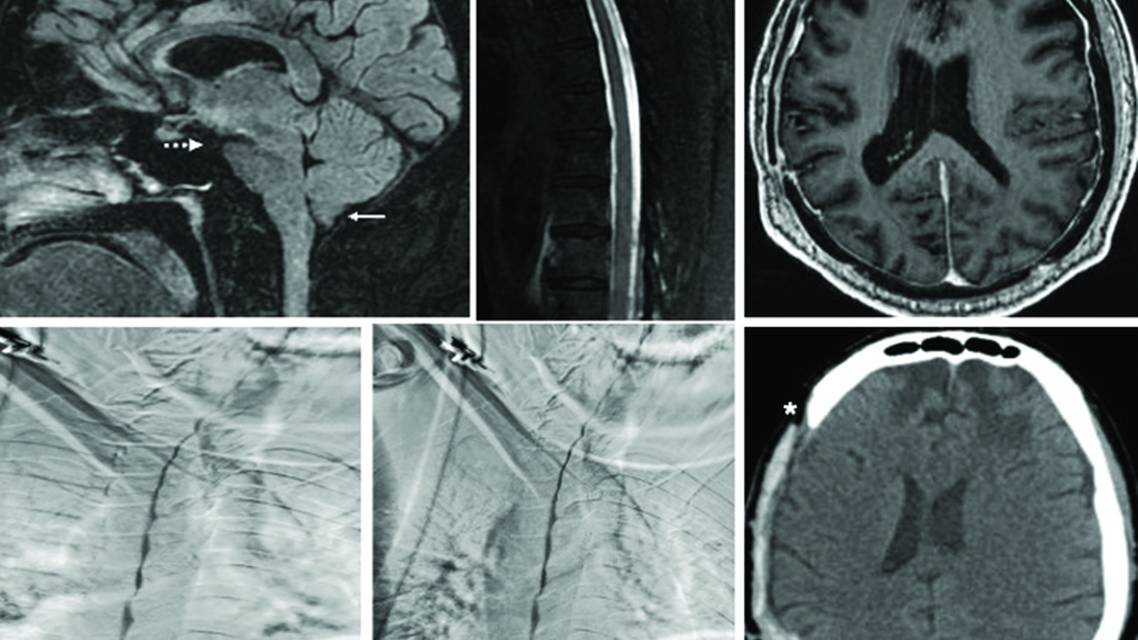

Evaluation revealed a relatively low opening cerebrospinal fluid (CSF) pressure (80 mm of water), lower cranial nerve palsies, and ataxia. Contrast-enhanced MRI of the brain and spine demonstrated brainstem sagging with significantly decreased mamillopontine distance (3 mm), tonsillar herniation, and mild pachymeningeal enhancement of cerebral convexities (Figure 1, A and C), without any spinal longitudinal epidural collection (Figure 1B). To rule out any spinal longitudinal epidural collection and negative spontaneous intracranial hypotension (SIH), a dynamic prone CT myelogram (CTM) was performed but failed to demonstrate a CSF leak or delayed contrast excretion in the renal pelvis. Therefore, dynamic digital subtraction myelography (DSM) in the right followed by left lateral decubitus positions was also performed, but the results were unremarkable (Figure 1, D and E).

Figure 1. Sagittal 3-dimensional fluid-attenuated inversion recovery MRI scan shows evidence of brainstem sagging with tonsillar herniation (white arrow) and a reduced mammillopontine distance (broken white arrow), consistent with spontaneous intracranial hypotension (A). Spinal MRI screening shows no evidence of spinal longitudinal extradural cerebrospinal fluid (CSF) collection (B). Axial contrast-enhanced T1 MRI scan shows postcranioplasty changes with diffuse dural thickening and enhancement (C). Lateral decubitus digital subtraction myelography of the left (D) and right (E) sides shows no obvious CSF leak or CSF–venous fistula. Axial CT scan of the head shows a cement cranioplasty graft with improper opposition (white asterisks) (F).